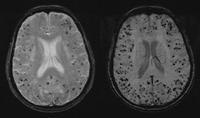

AVC hemorrágico

Mulher com 80 anos de idade e diversos focos pontuados de hipointensidade (pontos pretos) na sequência de ressonância nuclear magnética (RNM) por ecogradiente (GRE) (esquerda), sugerindo diversos microssangramentos lobares causados por angiopatia amiloide cerebral. Sequência (direita) de imagens de RNM por susceptibilidade ponderada demonstra diversos microssangramentos adicionais não observados na sequência GRE

Arquivos de casos pessoais do Foothills Medical Center; usados com permissão